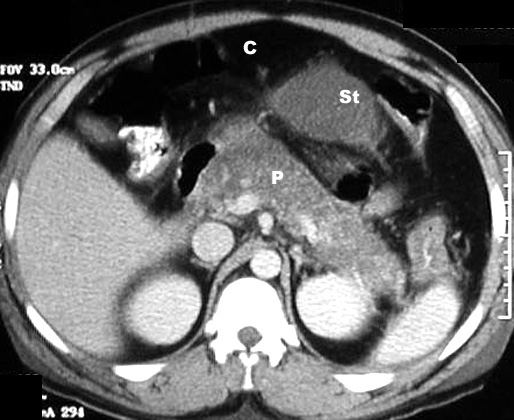

CT scan in Acute Pancreatitis

Post Contrast CT findings reveal diffusely enlarged pancreas with low density from edema.

C:  Colon

St: Stomach

P:  Pancreas